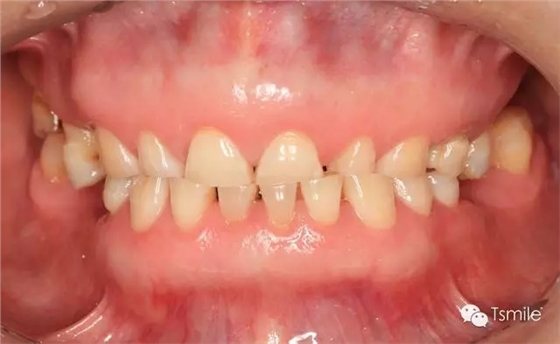

圖1: 夜磨牙導(dǎo)致的牙列重度磨耗

物理因素是指不同物體對(duì)牙齒表面的機(jī)械磨擦而導(dǎo)致的牙齒表面硬組織的缺損。物理因素導(dǎo)致的牙列重度磨耗按照摩擦牙齒表面的物體的不同主要可以分為以下兩類: 磨耗是指在下頜的功能運(yùn)動(dòng)(咀嚼食物等)或副功能運(yùn)動(dòng)(夜磨牙、緊咬牙等)過(guò)程中上下頜牙齒和牙齒之間的機(jī)械摩擦而導(dǎo)致的牙齒表面硬組織的缺損。 磨耗患者一般有特定的飲食習(xí)慣,如喜吃硬食、嚼檳郎等,這些飲食習(xí)慣導(dǎo)致咀嚼時(shí)咬合力過(guò)大,或者牙齒咬合面之間粗燥的事物導(dǎo)致牙面承受過(guò)度的機(jī)械摩擦;磨耗患者一般還有夜磨牙、緊咬牙等副功能運(yùn)動(dòng)病史。